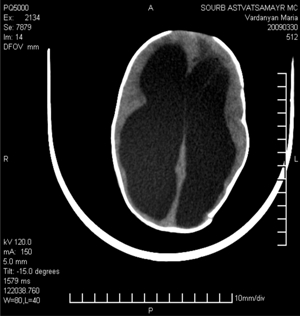

В настоящее время КТ занимает доминирующее положение среди методов диагностики гидроцефалии. КТ (рис. 1) помогает визуализировать мозговое вещество, ликворосодержащие полости, определить форму и выраженность гидроцефалии, характер деформации ликворосодержащих структур, степень декомпенсации ликворообращения и причины расстройства циркуляции СМЖ, позволяет контролировать результаты лечения.

Рис. 1. Томограмма больного с врожденной гидроцефалией

По данным КТ были выявлены следующие формы гидроцефалии: внутренняя – у 152 больных, наружная – у 8, смешанная – у 46, асимметричная и локальная – у 10 больных, определены формы внутренней гидроцефалии: тетравентрикулярная, тривентрикулярная, би-вентрикулярная, моновентрикулярная.